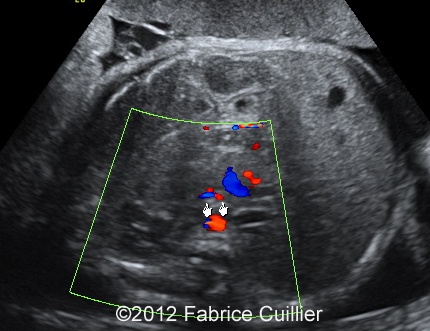

At 32 weeks, the aspect of the intestinal dilatation changed. Low digestive obstruction was suspected (Image 2, 3), with important aggravation at 35 weeks (Image 4). Mesenteric artery and vein had a physiological position (Image 5). Fetal ears and face were normal. Corpus callosus was present (Image 6). The extremities were also normal. Sex was male with bilateral hydrocele (Image 7). Abdominal fetal MRI was performed (Image 8, 9).

Image 5: Mesenteric artery and vein had a physiological position.

8A